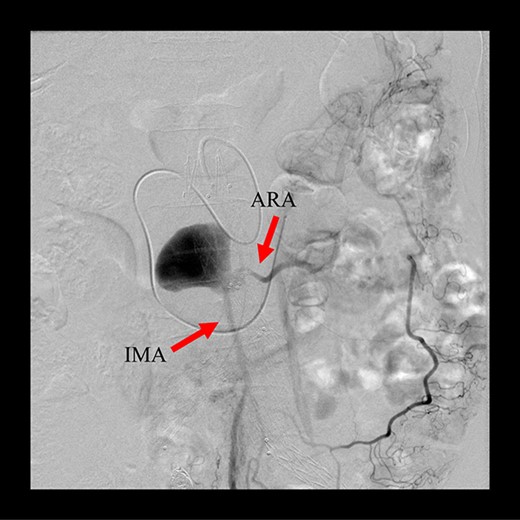

Angiography for decision-making revealed a type II endoleak from the IMA to the AAA, but no other visible endoleak (Fig. 2). Based on these findings, we planned additional EVAR for left CIAA, which was thought to have enlarged in natural course, and IMA embolization for the type II endoleak associated with sac enlargement. A staged strategy was devised. IMA embolization was planned several days after EVAR. Sac angiography from the IMA via Riolan’s arcade showed a flow-through endoleak to the ARA as a drainage artery (Fig. 3). Based on this finding, we embolized the ARA and the IMA with coils via Riolan’s arcade (Fig. 4). Selection and embolization of the drainage artery were technically feasible because of the flow from the IMA to the ARA. No deterioration of renal function due to ARA embolization was observed. One year after treatment, a CT scan demonstrated that the sac shrank to 42 mm with no evidence of a continuing endoleak (Fig. 5).

Angiography 8 years after EVAR demonstrated a type II endoleak from the IMA.